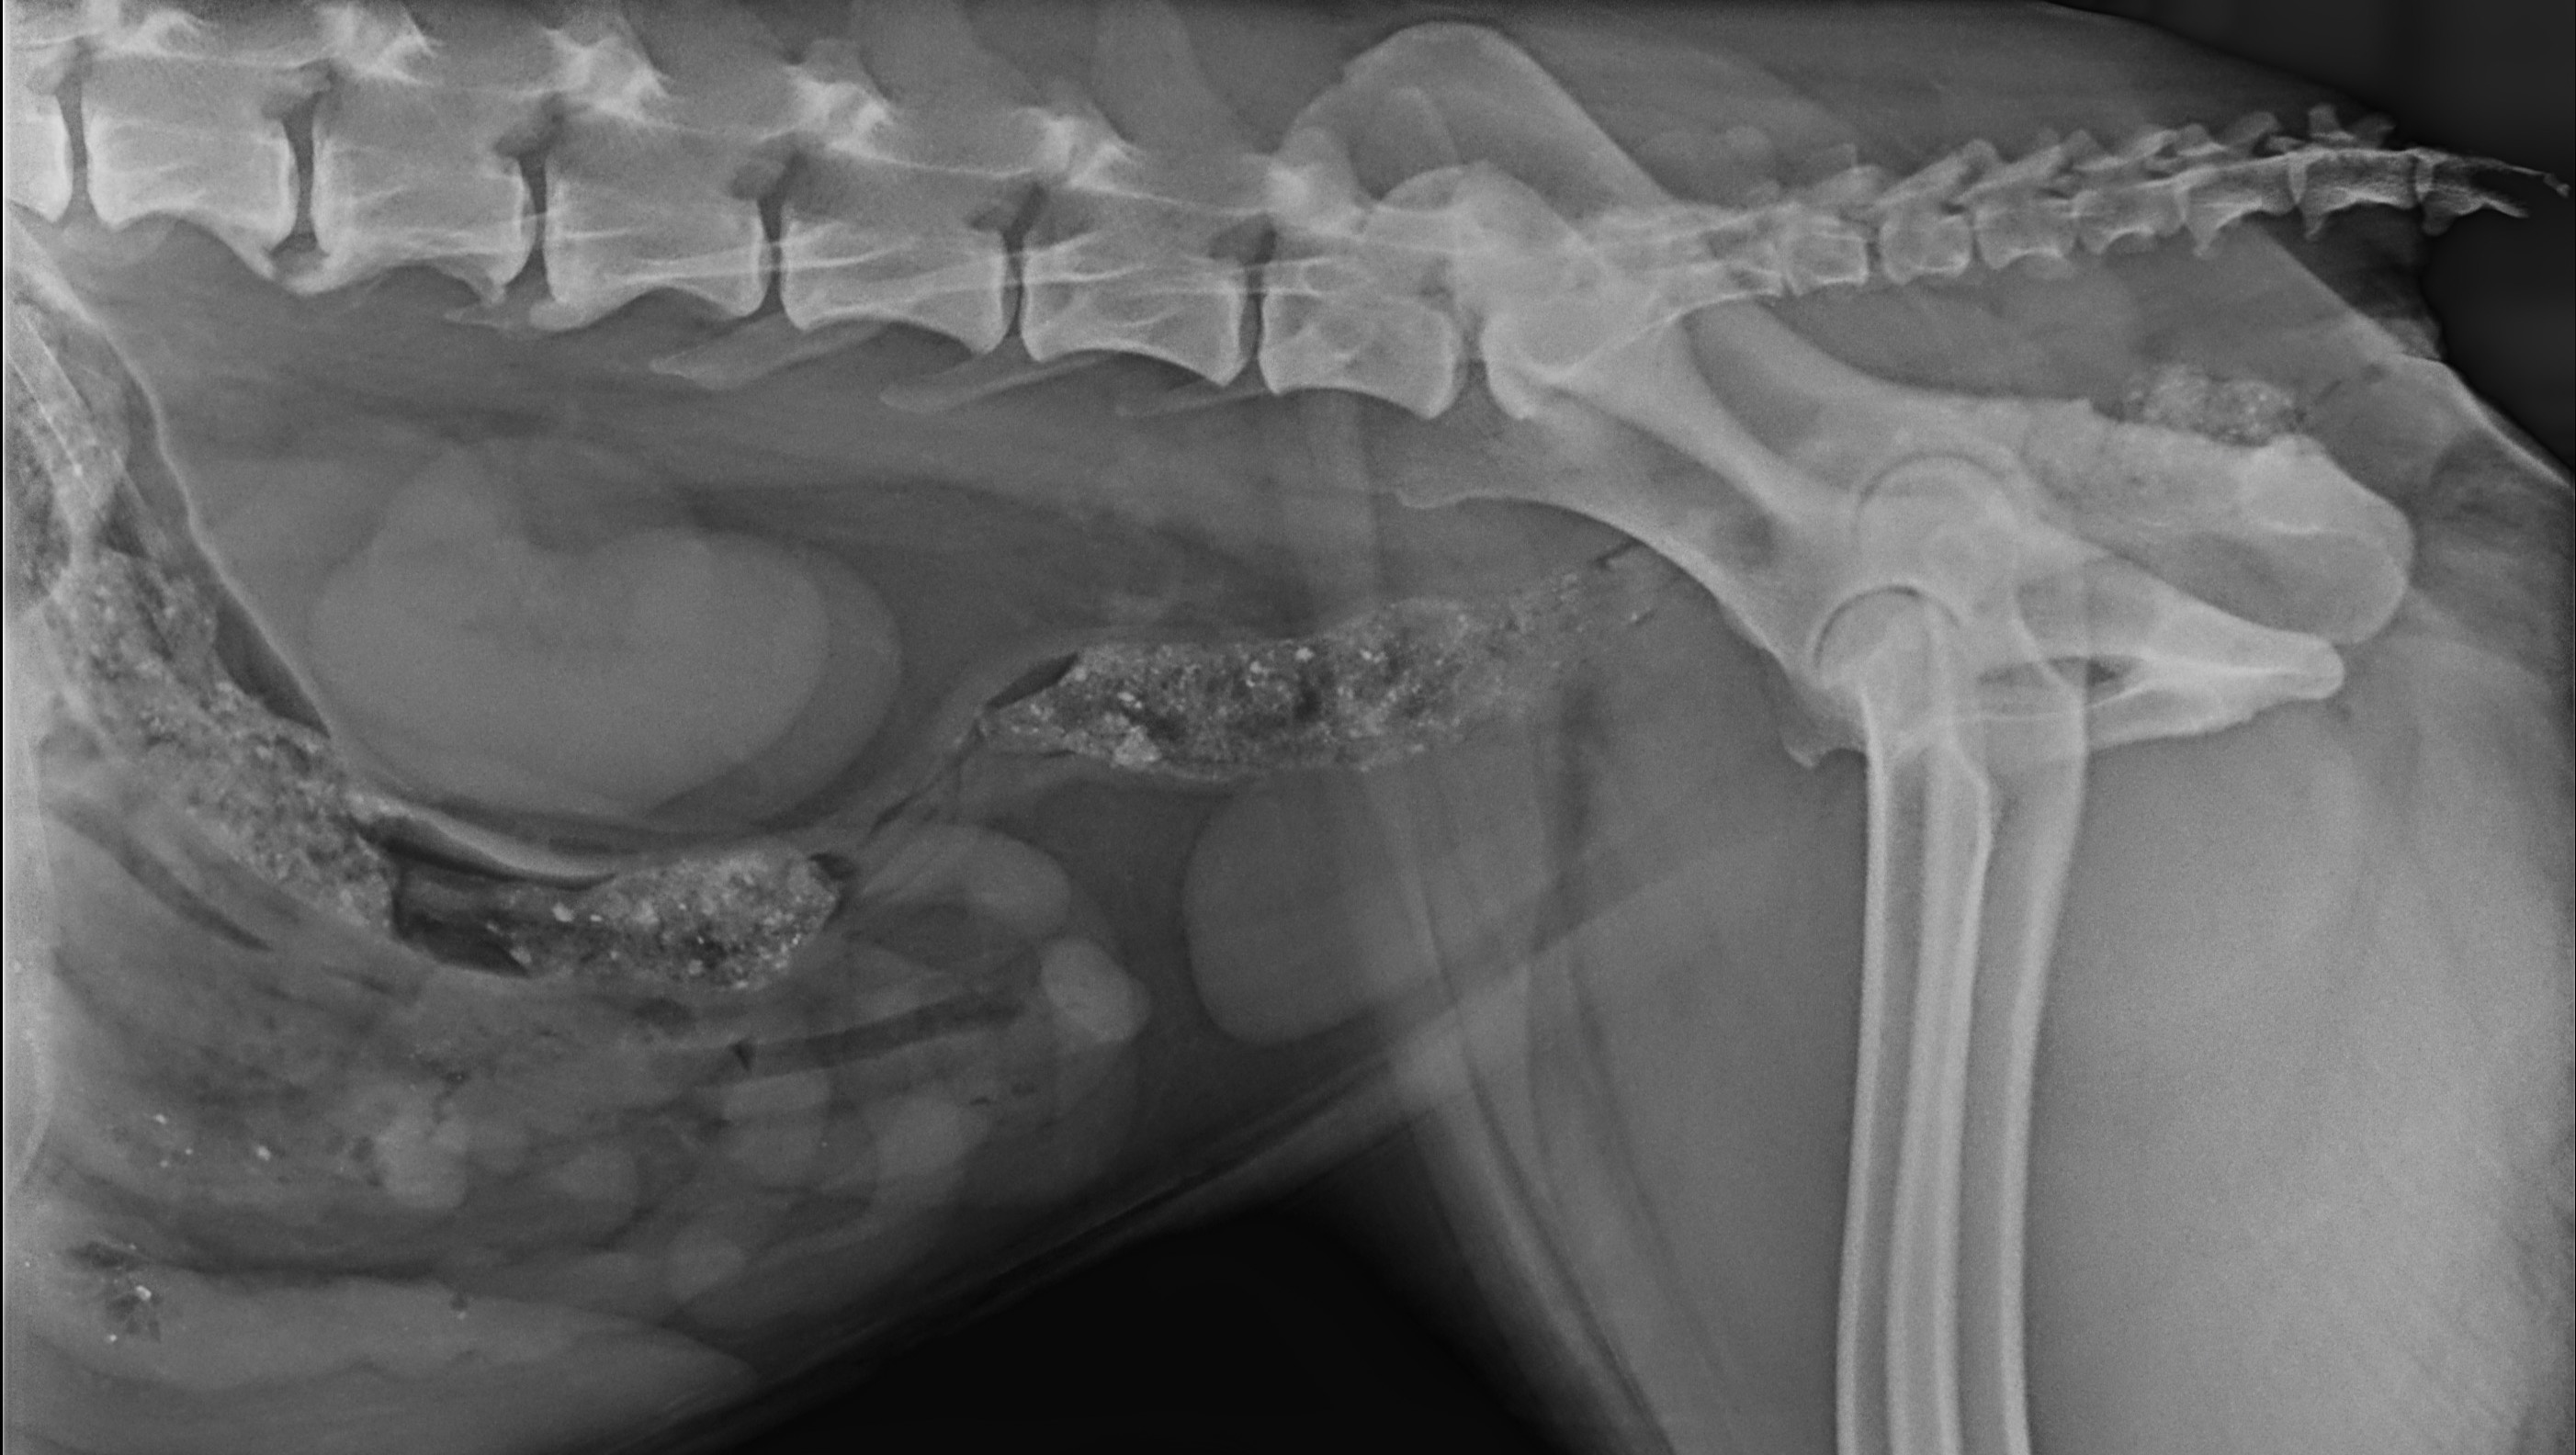

She has been by my side for 10 wonderful years, filling my life with love, loyalty, and joy. Frida isn’t just a pet, she is my longest relationship and bestest of friends. Sadly, she was recently diagnosed with spondylosis, a painful condition where bony spurs form along the spine, bridging several disc spaces. This makes every step a challenge, she is starting to drag her hind legs and robs her of the simple pleasures she once loved, like playing fetch (ball is life) or going on long walks. Eventually, she will stop walking altogether.

I was recently fired from my job and can’t afford the upcoming bills. We are already doing physical therapy to strengthen her muscles and help her mobility, but her veterinarian has recommended surgery to relieve the pressure caused by the bony growths, followed by post-surgery care and rehabilitation to give her the best chance at recovery. With the right treatment plan, Frida will keep being a happy dog.